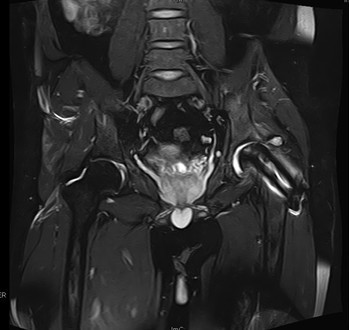

查体:左髋外侧可见一约25cm手术瘢痕,其上可见一点状结痂,左腿较右腿短缩,左腿肌肉较右腿萎缩,步态异常。左髋部无压痛,左腿外侧感觉异常,以左膝外侧为重,左髋外侧叩击痛,左足背动脉搏动未扪及异常。左下肢较右下肢短缩约2cm,左髋关节活动受限,其余各关节未见明显异常。 辅查:MRI示左股骨头坏死

诊断:左股骨头股骨颈粉碎性骨折切开复位内固定术后坏死 治疗:择期行关节置换术